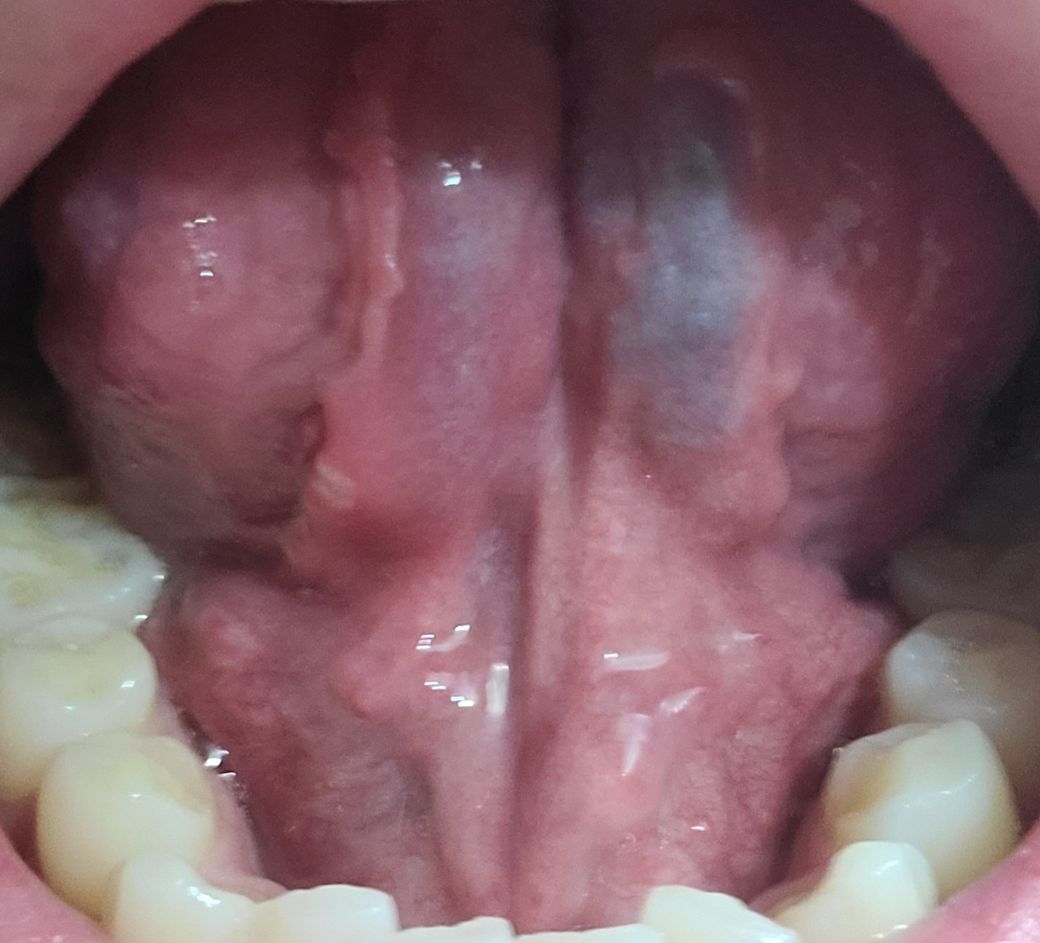

어제부터 혀밑이 아파서 보니 혀 양쪽으로 돌기같은것이 올라와있고 혀 밑에서도 올라와있습니다. 간단한 구내염인가요? 알려주세요ㅠ

사진으로 볼때는 특별하게 이상이 있어보이지 않습니다.

우너래 있는 구조물로 사료되니 걱정말고 지켜 보시는것을 추천 드립니다.

돌기들의 경우 정상적으로도 발생되어 있을 수 있습니다.

하지만 해당 부분에 설염 등으로 인해서 통증이 유발될 수 있으며, 가글 및 수분섭취 등으로 건조함을 막아주시고 그럼에도 증상호전이 없을 경우는 이비인후과 및 치과에서 진료를 받아보시는 것을 추천드립니다.